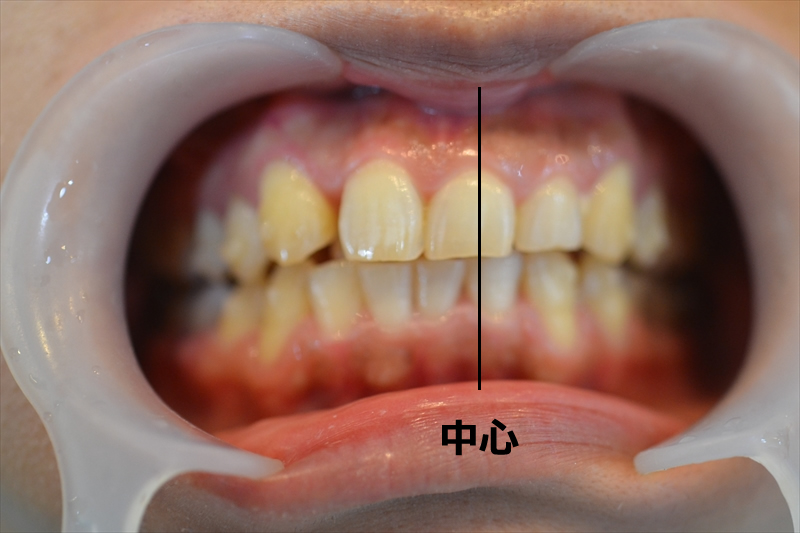

上下の噛み合わせが深く、上の前歯が下の前歯を覆い隠す状態となる過蓋咬合(ディープバイト)でした。

それにより、右2番目から左の歯は全て半歯分右にズレてしまっていました。

上顎の嚙み合わせに合わせるように下顎も右にズレてしまっています。

※上下ともに中心から4mmズレています。

患者様も顔の歪みを気にされており、このズレが要因の一つだと考えられます。

しかし、噛み合わせは悪くない状態でした。(ズレた状態で噛み合っている)